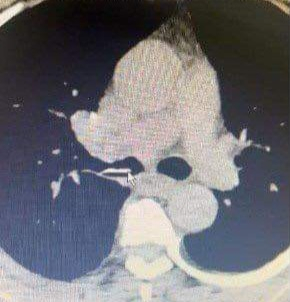

Sau khi tiến hành thăm khám, người bệnh được chỉ định chụp CT-Scanner. Kết quả phát hiện dị vật tại phế quản gốc phải. Nhanh chóng người bệnh được chỉ định gây mê nội soi phế quản để gắp dị vật.

Mảnh xương tại vị trí phế quản gốc phải của người bệnh trên phim chụp CT-Scanner. Ảnh : Bệnh viện Việt Nam – Thụy Điển Uông Bí.